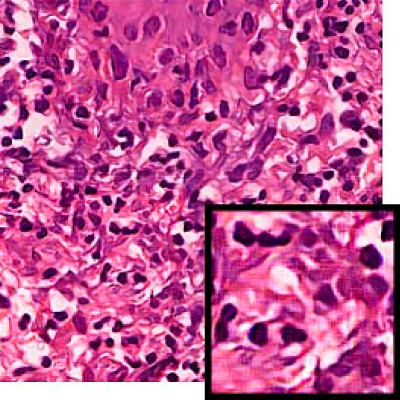

Leishmaniasis background and histology presentation. The World Health Organization (WHO) has selected cutaneous leishmaniasis as a neglected tropical disease (NTD) with growing, uncontrolled, and ignored infection affecting millions of people every year [14, 9]. It is unfortunately one of the world’s most neglected poverty-related diseases, affecting the poorest people in developing countries and it is associated with risk factors like malnutrition, immune system deficiency, migration, inadequate education, illiteracy, gender inequality, and a shortage of services [1]. Furthermore, only eight countries in the world contribute to 90% of leishmaniasis cases: Afghanistan, Algeria, Brazil, Iran, Pakistan, Peru, Saudi Arabia, and Syria [12]. It is a vector-borne infection caused by the protozoan parasite Leishmania. The vector is the female sand-fly. The lesions of cutaneous leishmaniasis vary in presentation ranging from a single self-limited skin lesion to multiple large destructive and ulcerated lesions on mostly the exposed parts of the body such as face, forearms, and lower legs [2]. Skin biopsy is considered the gold standard method for confirmation of diagnosis. The presence of large epitheloid granulomas and small hematoxylinophilic LD bodies (that are round, uniform in appearance, intracytoplasmic and sometimes distributed around the outer rim of the vacuoles) is critical for diagnosis and confirmation of leishmaniasis [4]. Large granulomas are visible at 10X but the smaller hematoxylinophilic bodies (around 3-4mm in size) are usually visible at 40X and can easily be missed if they are few in number, leading to misdiagnosis. Specialized dermatopathologists are the only ones who can diagnose these accurately based on patient history, clinical features, and laboratory diagnosis. It is thus critical to share the digitized slides of these cases from rural poor remote areas with dermatopathologists (mostly residing in urban centers) for quick diagnosis and accurate management of the patient.

We demonstrate our WSI creation workflow on Leishmaniasis cases, as shown in Figures 1 and 4. An expert pathologist reviewed the cases and annotated granulomas as well as LD bodies on the stitched images and our generated images in Figure 4. To show generalizability of our approach, we also show results on core biopsies of breast, duodenum, stomach, liver, and lymph nodes (Figure 5).